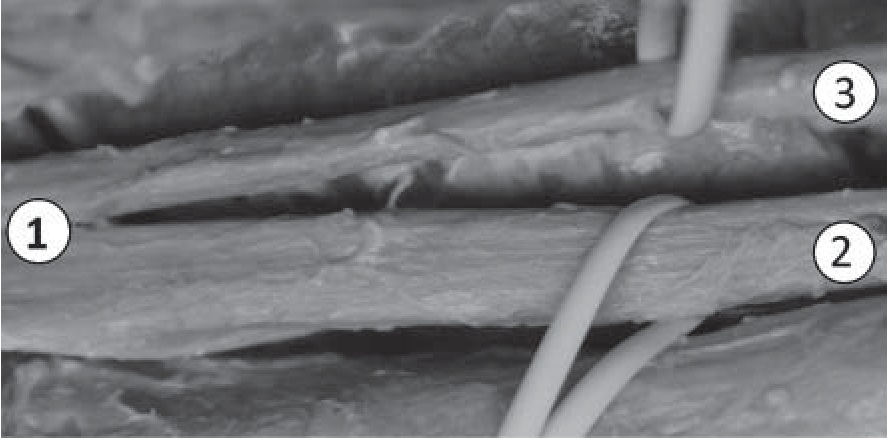

После формирования и отхождения латерального кожного нерва икры общий малоберцовый нерв направляется вниз и латерально, огибая задний край головки малоберцовой кости, и входит в туннель, образованный камбаловидной мышцей и двумя головками длинной малоберцовой мышцы (рис. 3).

Рис. 3. Формирование общего малоберцового нерва на уровне головки малоберцовой кости (препарат, изготовленный методом полимерного бальзамирования): 1 – ствол общего малоберцового нерва; 2 – латеральный кожный нерв икры; 3 – головка малоберцовой кости; 4 – длинная малоберцовая мышца; 5 – камбаловидная мышца